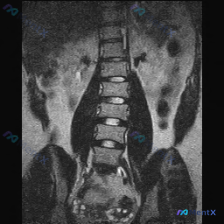

整理到一张腰椎MRI-T2加权冠状位的影像资料,核心发现确实有脊柱侧弯(凹侧指向右侧,胸腰段下为主),但看完分析后觉得,单纯盯着侧弯可能会漏更关键的问题。

- 序列:腰椎生理曲度消失,明显侧弯;

- 椎体:多节段中下段腰椎塌陷、楔形变,边缘骨质增生;

- 椎间隙:多节段显著狭窄,T2信号丢失(椎间盘脱水/破坏);

- 骨髓信号:最显眼的是这个——下胸到腰椎椎体不是均匀高信号,而是弥漫性混杂、斑片状低信号;

- 椎旁:腰大肌信号尚可,但解剖位置因侧弯变形。

目前给出的鉴别方向覆盖了:退行性侧弯、骨质疏松伴骨折、感染(结核)、肿瘤(转移/骨髓瘤/淋巴瘤)。